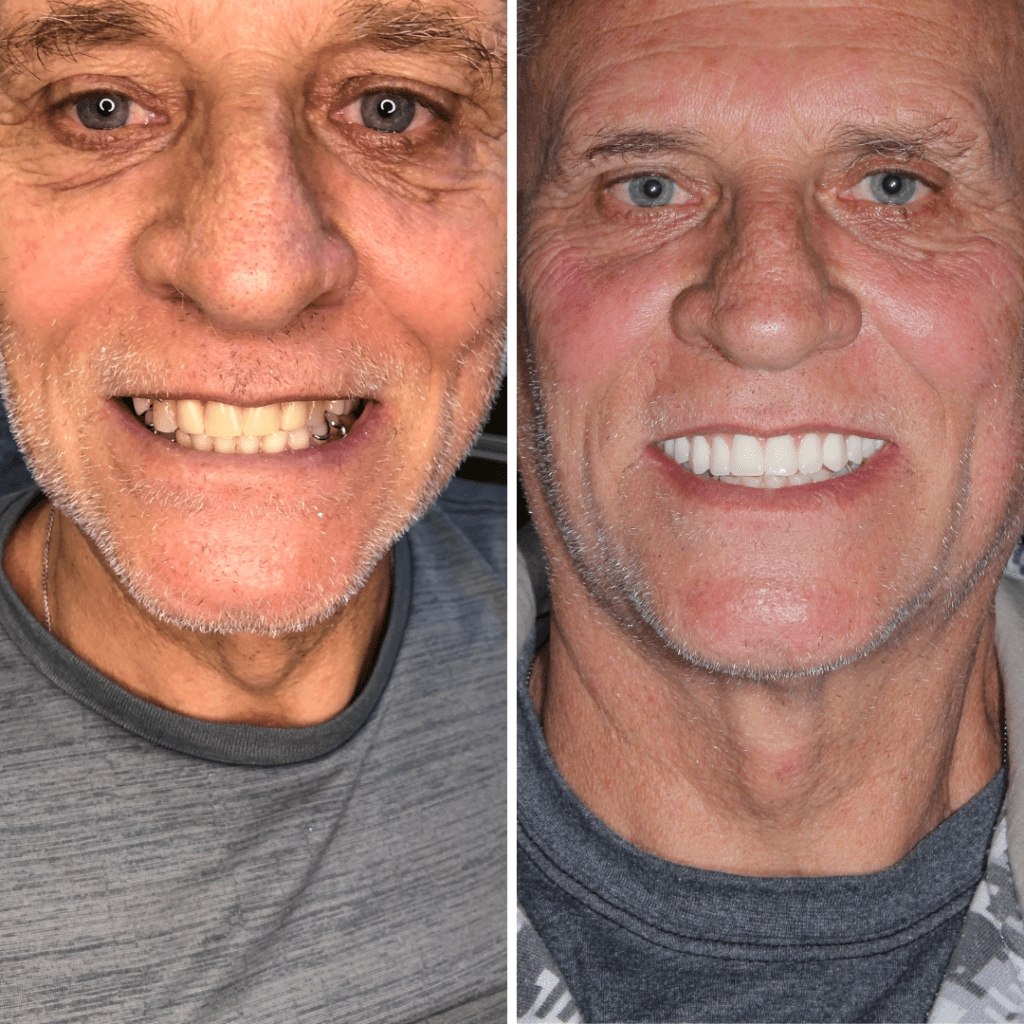

É uma dentadura totalmente fixa sobre implantes e é a prótese que mais fica próxima da sensação de dentes naturais. Ela não é removível, fica fixa na boca.